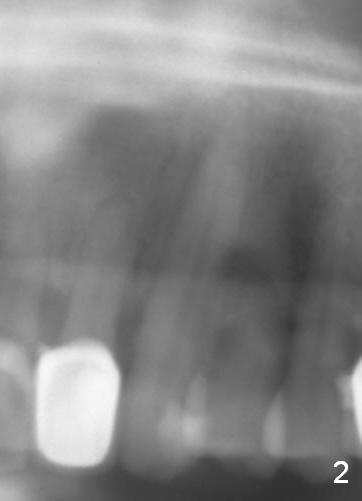

A 57-year-old man has multiple restoration. There was a fistula mesiobuccal to #11 a year ago (Fig.1,2). There is acute apical infection lately. The pulp is non-vital. Apex locator is sensitive. Two PAs are taken with #15 file at 29 mm and 33 mm (Fig.3,4). The canal is debrided until #40 hand file. The master cone with length of 28 mm is inserted below the landmark (Fig.5). Panoramic X-ray is taken for final confirmation (Fig.6).